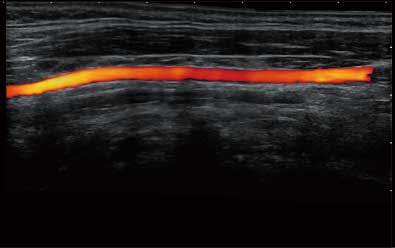

• Wi-Flow

通过对组织运动信息、血流信号及背景噪声进行准确智能的阈值判定,高效提取出微弱血流信号,获得高灵敏度和空间分辨率的血流图像,为临床提供更加真实和丰富的诊断信息。